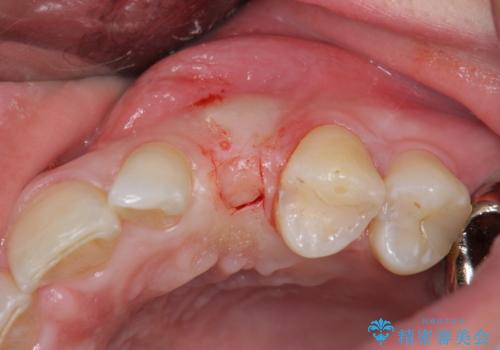

骨造成を伴う 前歯部インプラント治療

- 欠損している前歯のインプラント治療を希望され来院されました。

適切なインプラント埋入を行い、不足している骨量を補うため骨の造成を併用したインプラント治療を計画します。

前歯のインプラント治療は骨量・歯肉の厚み・インプラントの方向をしっかりと計画することで、審美的で長持ちを期待できるような仕上がりとなります。

- 外科手術のため、術後に痛みや腫れ、違和感を伴います